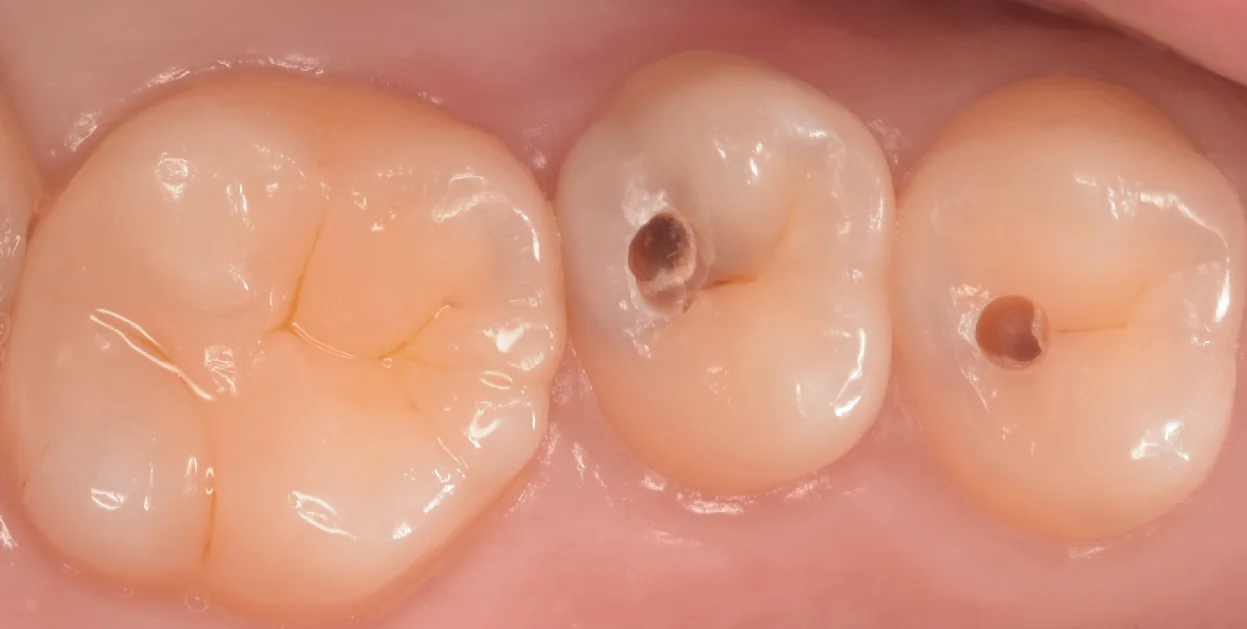

まずは術前からです。

画像上で右二つの治療を今回行いました。

ちなみに左の大きな歯についてはこの1ヶ月程前に治療を行ったものになります。

なんとなく歯の内部が黒っぽいのがわかりますかね?